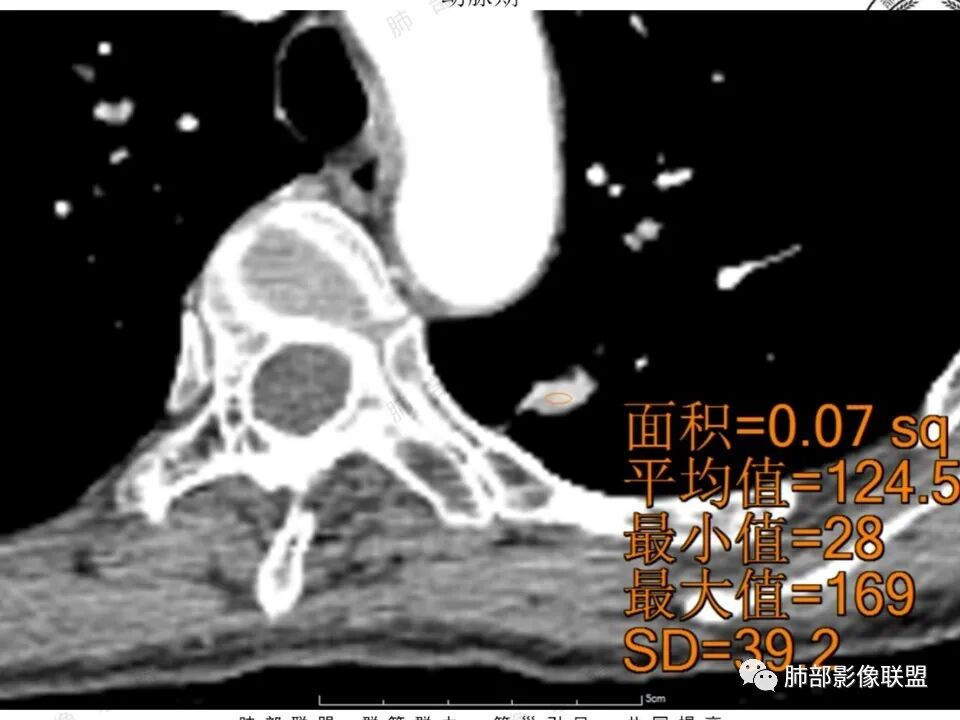

女,41岁,体检发现肺部结节。左肺上叶长形病灶,具有轻度膨胧感,刀切尖角征,胸膜粘连,早期强化见薄环强化征象,后期有延迟强化特点。病灶周围不是很干净。考虑结核肉芽肿或炎症肉芽肿。

左肺上叶尖后段实性结节,边缘有清晰磨玻璃,胸膜有牵拉凹陷,明显强化,CT值超过主动脉,考虑血管畸形(周围磨玻璃可能是出血),鉴别IAC(影像表现符合,强化不符)

41岁女性,左肺上叶不规则结节,边缘见似清非清的磨玻璃影,叶间裂牵拉。整体病灶边缘平直,强化明显。另左上叶外侧尚有一磨玻璃结节(蘑菇兄弟?),考虑炎性肉芽肿可能性大。强化太明显让人很纠结,会不会存在CD,但边缘又有磨玻璃影;腺癌、结核、隐球都没有见过强化这么明显的,强化程度与主动脉基本一致,不会是动静脉畸形吧。

功能学(高强化)形态学的取舍,形态学(ggo),高强化不能除外ca

形态上看肯定不敢排除ca,就是强化这点,以往没认识到

晨读反思:1.边缘磨玻璃还是比较清楚;2.有收缩力;3.强化明显提示内部有血管,说明破坏力不强。

1.中年女性,体检发现;2.左肺上叶后段长条形结节灶,边缘有膨隆,也有收缩,腺癌和炎性结节都可以,但是周围见边界清楚磨玻璃影强烈提示腺癌可能性。3.显著强化的肺结节,无论如何都应当引起我们的高度重视!尽管炎性病灶和新生物都可以,尽管强化程度不能作为诊断癌肿的依据。

4.本例结节强化程度明显低于主动脉,也缺乏血管畸形的典型的迂曲结构,血管畸形可能性不大。